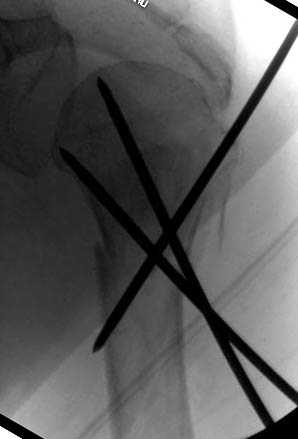

Наш недавний случай перкутанной фиксации "методом

Сиэтла" спицами 2.8 мм с резьбой на конце.

Второй случай, для лечения перелома проксимального

плеча применили пластину "Hand Innovation"

http://www.handinnovations.com/pdf/S3_technique.pdf

Пластина имеет преимущества перед другими "Locking

Implants", потому что пластину можно уложить намного ниже чем другие пластины и имеется возможности проведения шурупов под 130 градусным углом, таким образом можно уменьшить операционный разрез в проксимальной части.

Прооперирован вчера на 13 день после поступления.

Больному 41 и из-за гемодинамической нестабильности в течение первых 7 дней был в реанимации под интубационной седацией.

Кроме перелома плеча у больного старый дистракционный перелом T12-L1 оперированный когда-то и кем-то, открытый перелом костей предплечья, который был прооперирован в ночь поступления, после I&D (хирургической обработки). Из-за разрыва селезенки при поступлении травма хирургами произведено удаление.

Дополнительно имеется перелом ацетабулума: задняя

колонна с полупоперечным переломом, и переломы костей лица.

На седьмой день зафиксирован перелом ацетабулума через задний доступ. Перед операцией для профилактики DVT, IVC фильтер, также получает Lovenox.

Из-за большого обьема конечности доступ к бугорку был затруднен, предварительно зафиксированный шуруп не удержал бугорок, поэтому фиксацию провели толстыми нитками. Состоятельность фиксации бугорка обычно проверяем во время операции, под рентген контролем проводится движения конечности, особенно приведение.